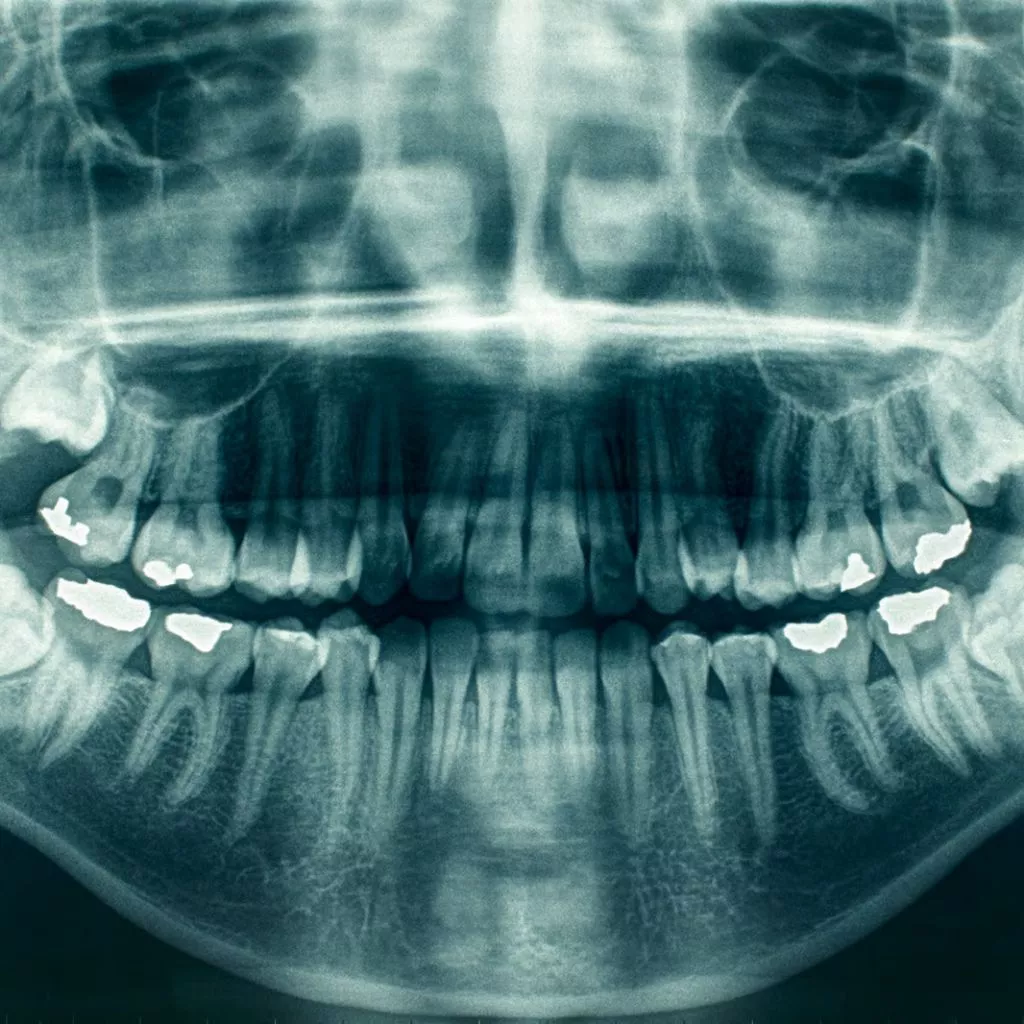

En Channel Islands Family Dental, utilizamos imágenes dentales intraorales de última generación para ofrecer evaluaciones precisas y detalladas de su salud oral. Esta avanzada tecnología nos permite capturar imágenes de alta calidad de sus dientes y encías, lo que permite planes de tratamiento precisos y personalizados. Visite nuestras ubicaciones en Oxnard, Santa Paula, Ventura, Newbury Park y Port Hueneme para descubrir cómo la imagen dental intraoral puede mejorar su experiencia de cuidado dental.